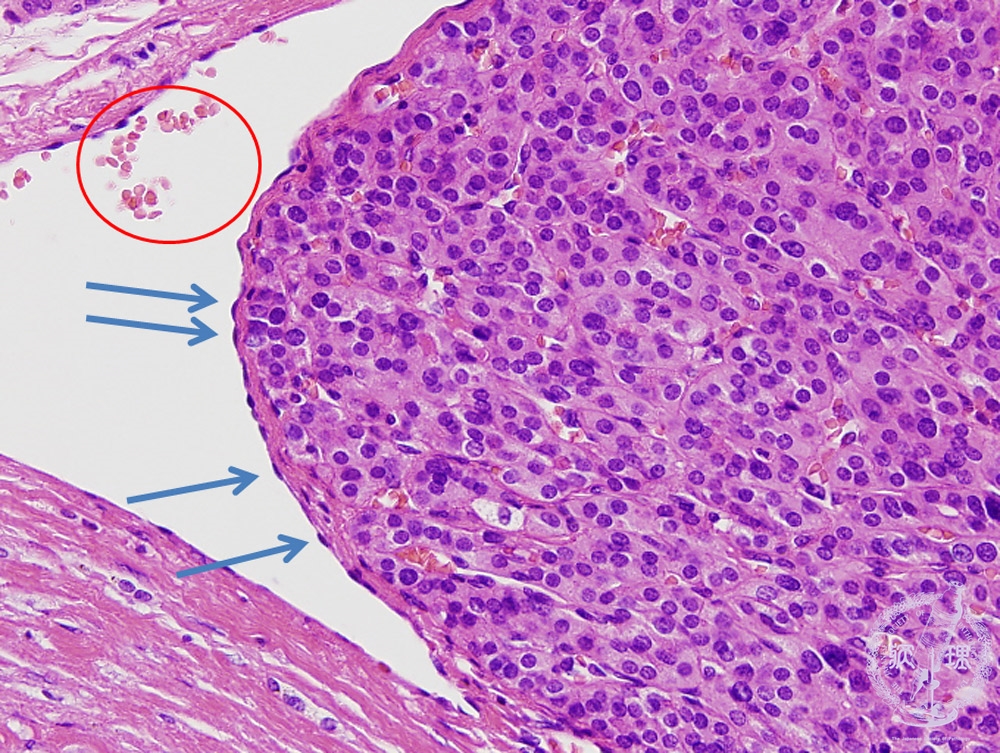

- (9)Follicular carcinoma of the thyroid

Microscopic findings (HE stain, middle power view). The presence of a tumor cell nest, covered by endothelial cells (arrows), in the blood vessel, can be interpreted as vascular invasion. It is recognized as a blood vessel lumen due to the presence of erythrocytes (red blood cells) indicated by the red circles.